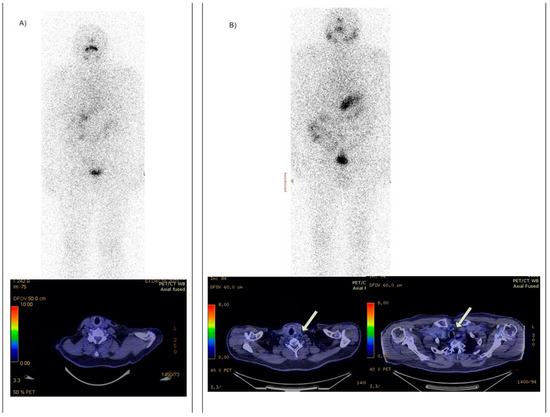

- Versari, A.; Sollini, M.; Frasoldati, A.; Fraternali, A.; Filice, A.; Froio, A.; Asti, M.; Fioroni, F.; Cremonini, N.; Putzer, D.; et al. Differentiated thyroid cancer: A new perspective with radiolabeled somatostatin analogues for imaging and treatment of patients. Thyroid 2014, 24, 715–726. [Google Scholar] [CrossRef] [PubMed]

- Roll, W.; Riemann, B.; Schäfers, M.; Stegger, L.; Vrachimis, A. 177Lu-DOTATATE therapy in radioiodine-refractory differentiated thyroid cancer: A single center experience. Clin. Nucl. Med. 2018, 43, e346–e351. [Google Scholar] [CrossRef]